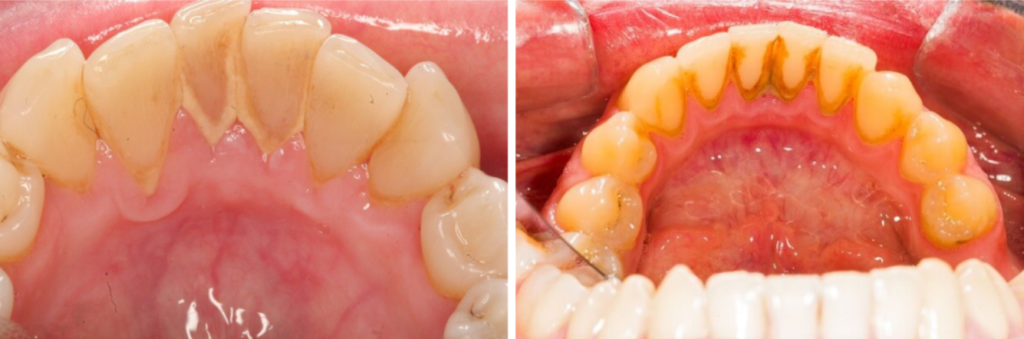

Cao răng là mảng bám màu vàng trên răng có ở thành trên răng và cả trên, dưới đường viền nướu. Mảng bám trên răng là lớp màng không màu, trơn nhầy bao phủ trên bề mặt răng do vi khuẩn và vụn thức ăn thừa tạo thành. Mảng bám có thể cứng lại thành cao răng. Để hàn chế việc hình thành mảng bám trên răng bạn nên vệ sinh răng miệng đúng cách như đánh răng 2 lần/ngày hoặc ngay sau bữa ăn, sử dụng tăm nước và chỉ nha khoa chuyên dụng để làm sạch răng miệng.

Có 2 loại cao răng là cao răng thường và cao răng huyết thanh. Cao răng thường có màu trắng đục hoặc vàng nhạt, ở những người hút thuốc lá chúng sẽ có màu sẫm hơn.

Cao răng huyết thanh hình thành khi cao răng thường gây viêm lợi. Vùng viêm tiết ra dịch viêm, gây chảy máu. Máu ngấm vào cao răng thường làm cao răng chuyển sang màu đỏ, mảng cao răng này gọi là cao răng huyết thanh.